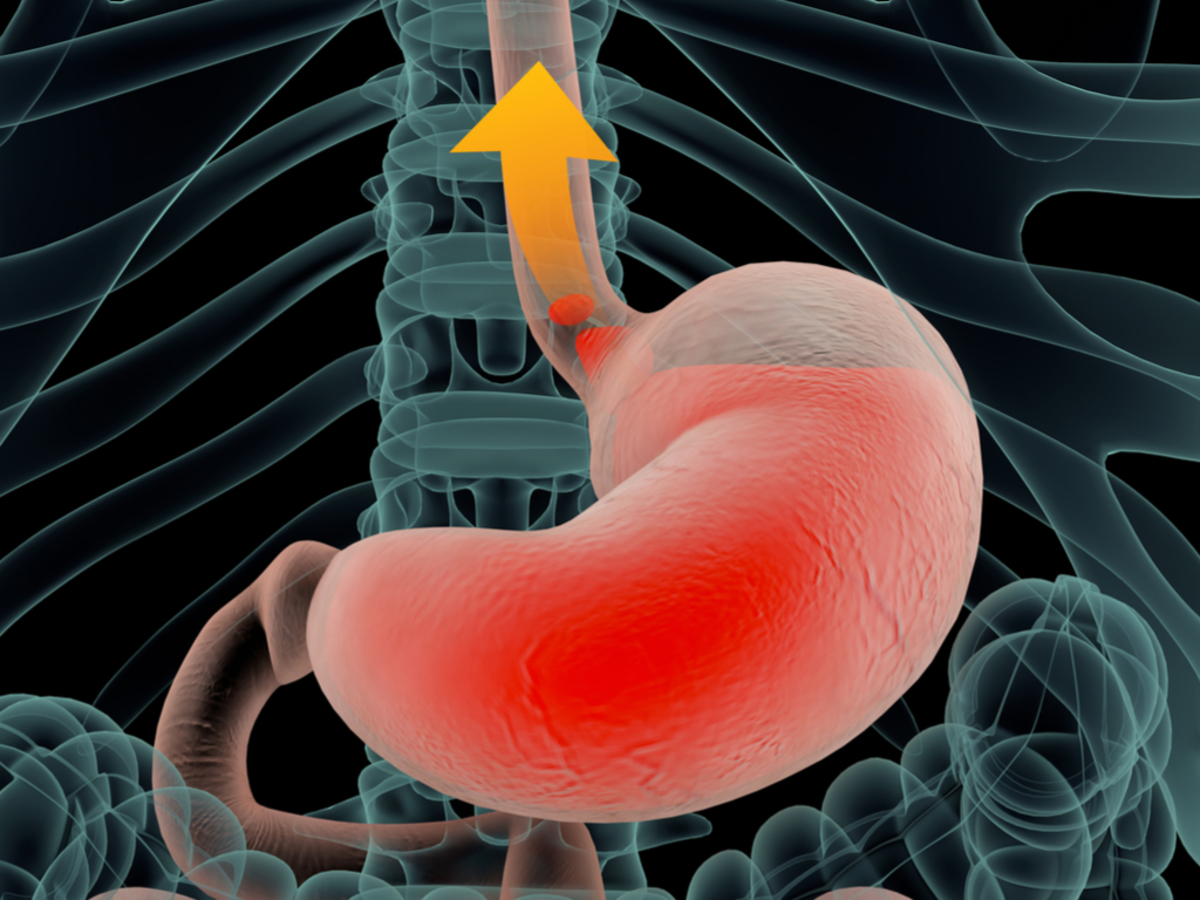

Информация и фотографии о хроническом гастрите и дуодените